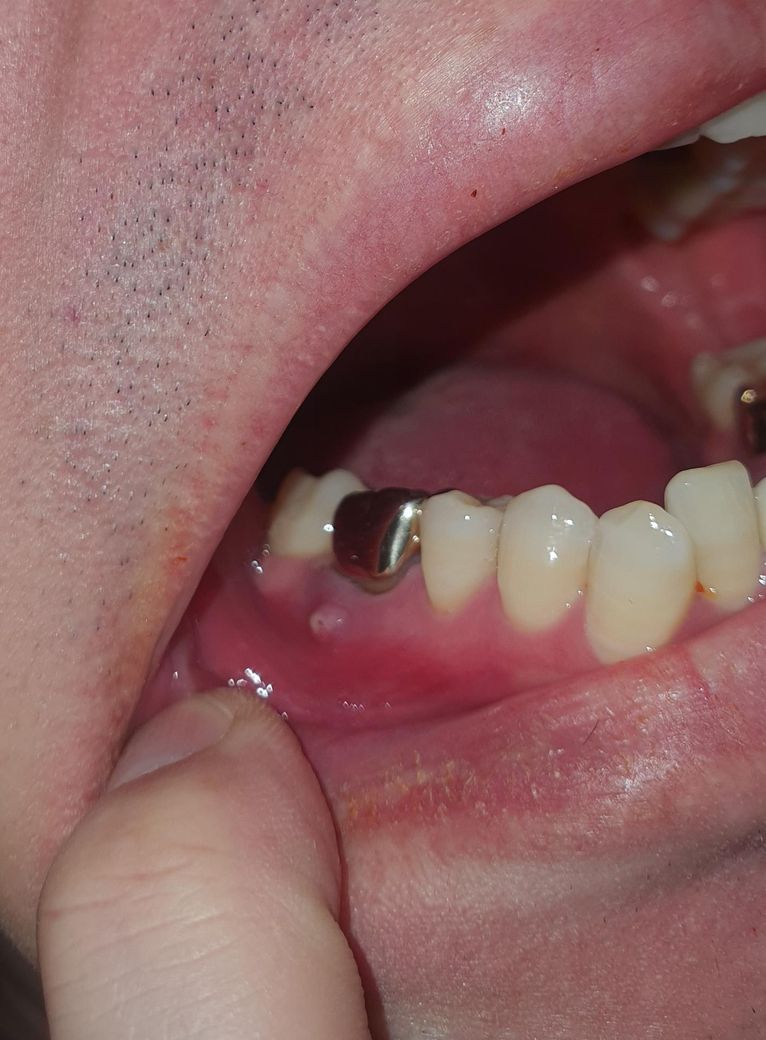

잇몸에 염증이 주머니가 생겼어요

발치밖에 방법이 없나요??

알려주세요.. 치료가 가능한지요 치근단술이나 재신경치료로 치료가능한지요..